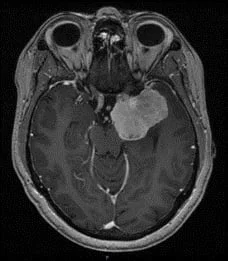

Un méningiome peut être diagnostiqué au scanner où il apparaît comme une masse ronde à la périphérie du cerveau, avec un épaississement de l’os au niveau de sa base d’insertion sur la méninge.

Il est plus fréquemment retrouvé sur une IRM sous forme d’une masse “blanche” après injection du produit de contraste intraveineux et entourée d’un œdème. Les méningiomes peuvent se rencontrer dans différentes localisations intra-crâniennes, plus ou moins facilement accessibles et qui conditionneront la technicité et les risques du geste qui vous sera proposé par votre chirurgien.

du rocher droit